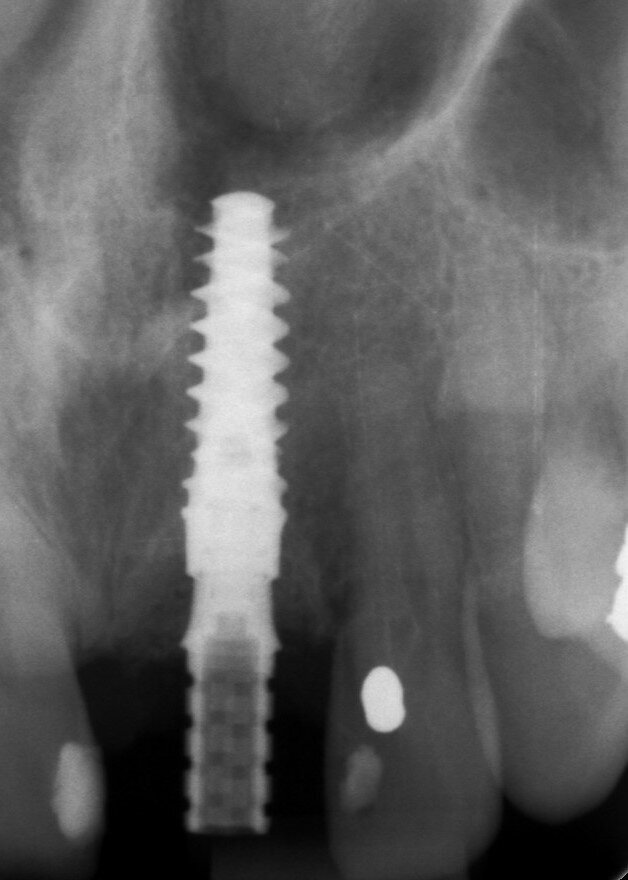

A 53-year-old female patient presented to the office with a fractured left central incisor which had been repeatedly bonded to a ceramic crown (Figs. 1 & 2). Anamneses and examination established good systemic and oral health, a well-balanced occlusion and no smoking habits. Cone beam computed tomography (CBCT) and a periapical radiograph showed external root resorption with very limited insertion into the alveolar bone, insufficient for adequate conventional intra-radicular post placement (Figs. 3 & 4). Considering that the fractured tooth was in the aesthetic zone, the patient requested restoration in the safest and fastest way possible.

Fig. 3: Pre-op periapical radiograph.

Fig. 4: Pre-op CBCT scan.

Intra-sulcular incisions were performed to release the marginal gingival fibres to allow a minimally invasive extraction. The socket was carefully cleaned to remove any ligament and debris left. Special attention was given to assessing the alveolar wall integrity. A distance of 3 mm was observed between the gingival margin and the labial wall margin. Implant bed preparation considered a medium-density bone workflow, starting with the needle drill aimed at the palatal wall to create an entry point for the next drills, creating an osteotomy that allows for a greater area of implant engagement (Fig. 5). The Ø 2.2 mm pilot drill was used to the respective implant length planned, followed by the use of an alignment pin to check the 3D orientation (Figs. 6 & 7). The Ø 2.8 mm and Ø 3.2 mm drills were used to finalise the osteotomy (Fig. 8). The site was then properly probed to assess for possible wall perforation. A 4 × 14 mm implant was placed, starting with the surgical handle engaging the apical part of the implant, following the same orientation as that of the needle drill and correcting the implant direction as it moved within the osteotomy (Figs. 9 & 10). Primary stability (45 Ncm) was achieved at the final position. After placement, the implant position was verified horizontally with an occlusal mirror and vertically with a surgical probe, and at this point, the abutment gingival height was selected (Figs. 11 & 12). A healing abutment was placed on to the implant (Fig. 13) to protect the connection so that granular bone substitute (Straumann XenoFlex) could be applied in the gap between the implant and labial wall. This was gently compacted in with the 2.8 mm side of the surgical probe (Figs. 14–16). Collacone (botiss biomaterials) was used to keep the bone granules away from the gingival margins in order to avoid softtissue fenestration and fibroblastic infiltration (Figs. 17 & 18).